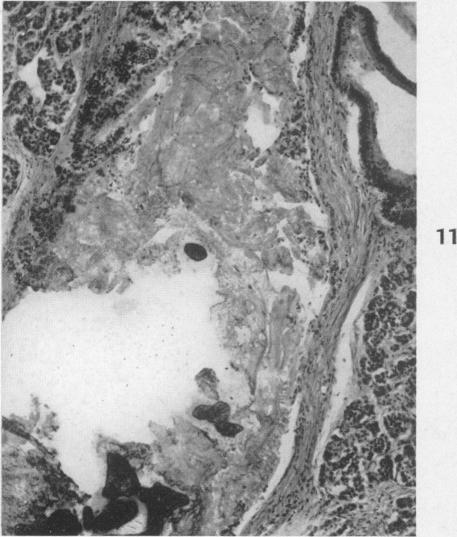

Chronic pancreatitis and lithiasis; a clinicopathologic study of 62 cases of chronic pancreatitis.

Am J Pathol. 1949 Nov;25(6):1227-47, incl 3 pl.